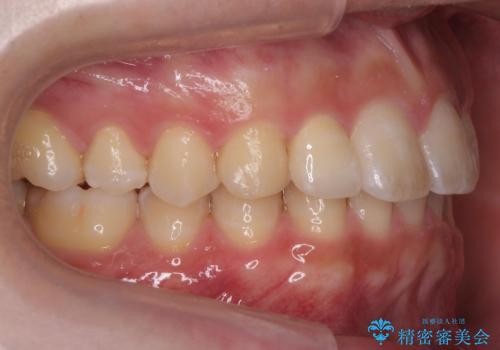

前歯のすき間 小さい歯がある 前歯の並びをきれいにしたい

- 前歯のすき間を気にして来院。

前から2番目の歯が小さく厚みがあったため(矮小歯)

矯正治療で1番目の歯を寄せて2番目の歯はセラミックで形をととのえています。

上下のかみこみがきつい場合で上にだけすき間がある場合は、上のすき間を閉じきるのは難しいことが多いです。

理由としては、すき間を閉じるには上の前歯は後ろに下がる形に動かないと無理なのですが、かみこみがきつい(かみ合わせがきつい、上下が深く咬んでいるともいいます)場合は、すぐ後ろに下の歯がかみこむためその動きができないためです。

さらに下の前歯にがたつきがある場合は下の前歯を後ろに下げること自体が難しくなるため、生まれつき歯の形が特殊な場合は、上のすき間を適切な位置にずらして、しかるべき歯にセラミッククラウンを被せて形態修正とスペースを埋めるというのが効率の良い治療方法と言えます。